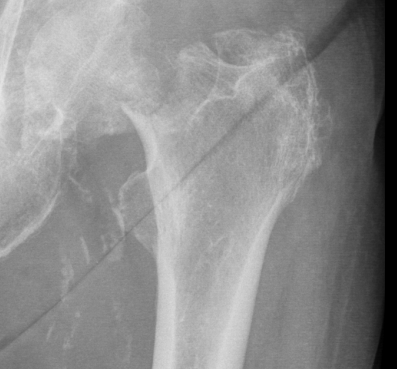

Hüftgelenksnahe Oberschenkelbrüche

Hüftgelenksnahe Oberschenkelbrüche bezeichnen die knöchernen Verletzungen des Hüftkopfes, des Schenkelhalses oder des Rollhügelmassivs (Trochanter major und minor). In der Regel ist ein Sturz auf das Hüftgelenk oder ein direktes Anpralltrauma dafür verantwortlich. Diese Frakturen sind typische Frakturen des höheren Lebensalters.

Die Patienten werden fast ausnahmslos über die Rettungsstelle in unsere Klinik eingewiesen. Klassische Symptome sind die Gehunfähigkeit, starke Schmerzen und ein nach außen verdrehtes Bein. Lokale Blutergüsse sind häufig vorhanden.

Modernste radiologische Diagnostik steht uns zur Klassifizierung der Fraktur und der sich daraus ergebenden Therapie zur Verfügung.